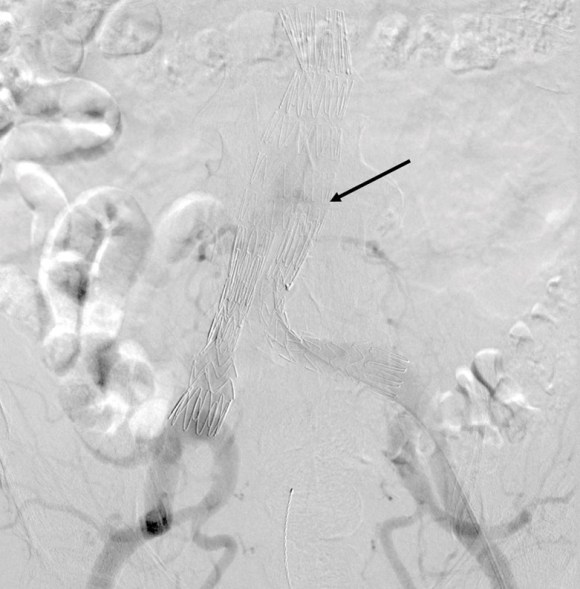

Initial aortography confirms the absence of a type I or III leak in early phase.

Later in the phase, the endoleak can be well seen, corresponding to the CTA.